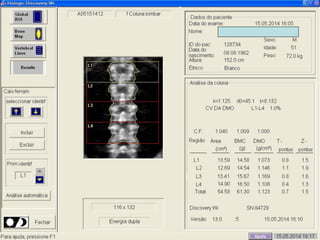

Aquisição (posicionamento)

Análise